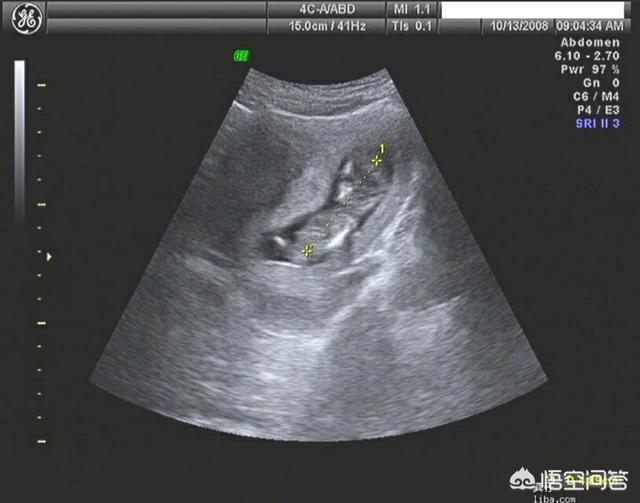

导读:顶臀径:又称头臀长(CRL),指胎儿从颅顶顶部到臀部外缘的距离。

头臀径长度往往用来推测胎儿孕周的,对于哪些月经不规则的宝妈来说,根据孕早期的B超测量值头臀径(CRL)来核实孕周还是很重要的。

简单的估算方法为:CRL(cm)+6.5=孕周

题主怀孕13周,根据公式由此推出此时头臀径长度约为6.5cm。如果头臀径长度差距大于1cm,建议核实孕周,以孕早期B超推测预产期为准。

总结,怀孕13周的胎儿头臀径在6.5cm左右,范围应该在5.5-7.5cm之间,此时宝妈的孕吐反应开始消退,宝妈可以享受短暂的舒心,因为孕20周后耻骨痛,腿抽筋,腰酸,失眠,便秘将接种而至。祝好孕。